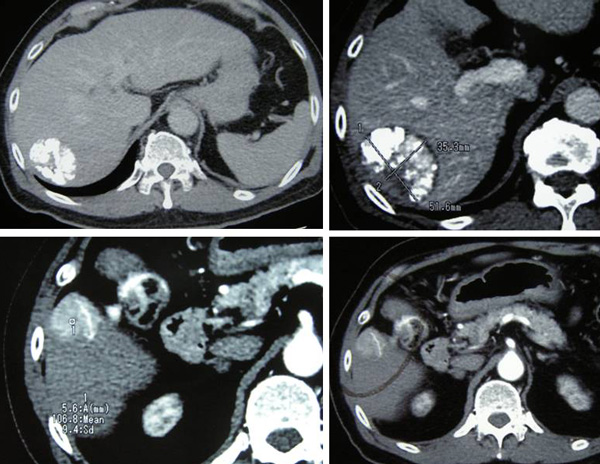

After two cycles of TACE, CT scan on 5 August 2010 showed the tumour has shrunk. The entire mass now measures 6.2 x 4.5 x 5.5 cm. The response was good with no evidence of metastasis.

CT scan on 6 October 2010 showed the tumour was significantly smaller in size, 4.7 x 5.4 x 4.6 cm. There was no evidence of recurrent or new lesions in the rest of the liver. No evidence of pulmonary metastataic deposits and no enlarged mediastinal or lymph nodes.

On 6 April 2011, a CT scan was performed. The previously treated mass in the right lobe of his liver measures approximately 3.5 x 5.1 x 4.8 cm in size. There is no associated hypervascularity seen with this mass. However, there is a new lesion in segment 5 of the right lobe of his liver. It is 3.1 x 2.3 x 3.6 in size.  This mass was not present on the previous scan of October 2010 and is suspicious of recurrent disease.

1. There is a 5.1 x 4.2 x 4.8 cm mass in segment 6 of the liver.

2. There is a 2.7 x 2.8 x 3.3 cm enhancing lesion in segment 5 of the liver.

3. There is an ill-defined enhancing lesion measuring about 2.3 cm in segment 8 of the liver.

4. There is a 2.5 x 2 x 2.1 cm mass just inferior to the right adrenal gland. Metastasis?

5. There is a 1.9 x 1.6 x 2.5 cm mass just inferior to the left adrenal gland. Metastasis?

6. There is a lytic lesion in the vertebral body of T12. Fracture of the superior endplate of T12 is noted. This probably represents a bony metastasis.